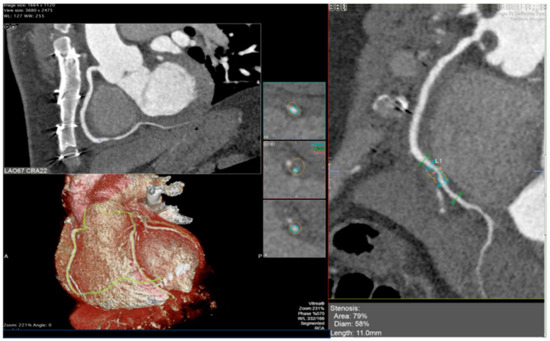

5.2. Cardiac Computed Tomography Angiography (CCTA)

- Budde, R.P.J.; Nous, F.M.A.; Roest, S.; Constantinescu, A.A.; Nieman, K.; Brugts, J.J.; Koweek, L.M.; Hirsch, A.; Leipsic, J.; Manintveld, O.C. CT-derived fractional flow reserve (FFRct) for functional coronary artery evaluation in the follow-up of patients after heart transplantation. Eur. Radiol. 2022, 32, 1843–1852. [Google Scholar] [CrossRef]

- Sharma, S.P.; Sanz, J.; Hirsch, A.; Patel, R.; Constantinescu, A.A.; Barghash, M.; Mancini, D.M.; Brugts, J.J.; Caliskan, K.; Taverne, Y.J.H.J.; et al. Temporal changes in CT-derived fractional flow reserve in patients after heart transplantation. Eur. Radiol. 2025, 35, 232–243. [Google Scholar] [CrossRef] [PubMed]